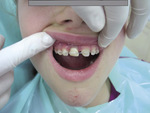

Ryc. 1. Stan w dniu zgłoszenia się pacjentki do Poradni Stomatologii Dziecięcej PUM – pusty zębodół po wybitym zębie 11.

Następnego dnia (23 maja 2014 roku) ok. godziny 9.00 pacjentka zgłosiła się do Poradni Stomatologii Dziecięcej PUM w Szczecinie. Ząb 11 był przechowywany w plastikowym pudełku z mlekiem. W badaniu stomatologicznym zaobserwowano stłuczenie bródki, nie było naruszenia ciągłości wargi górnej i dolnej, uszkodzenia dziąsła ani złamania wyrostka zębodołowego. Stwierdzono natomiast pusty zębodół po wybitym siekaczu (ryc. 1). Higiena jamy ustnej była zadowalająca. Wywiad ogólnomedyczny nie wskazywał na wystąpienie ogólnych i miejscowych przeciwwskazań do zabiegu replantacji.